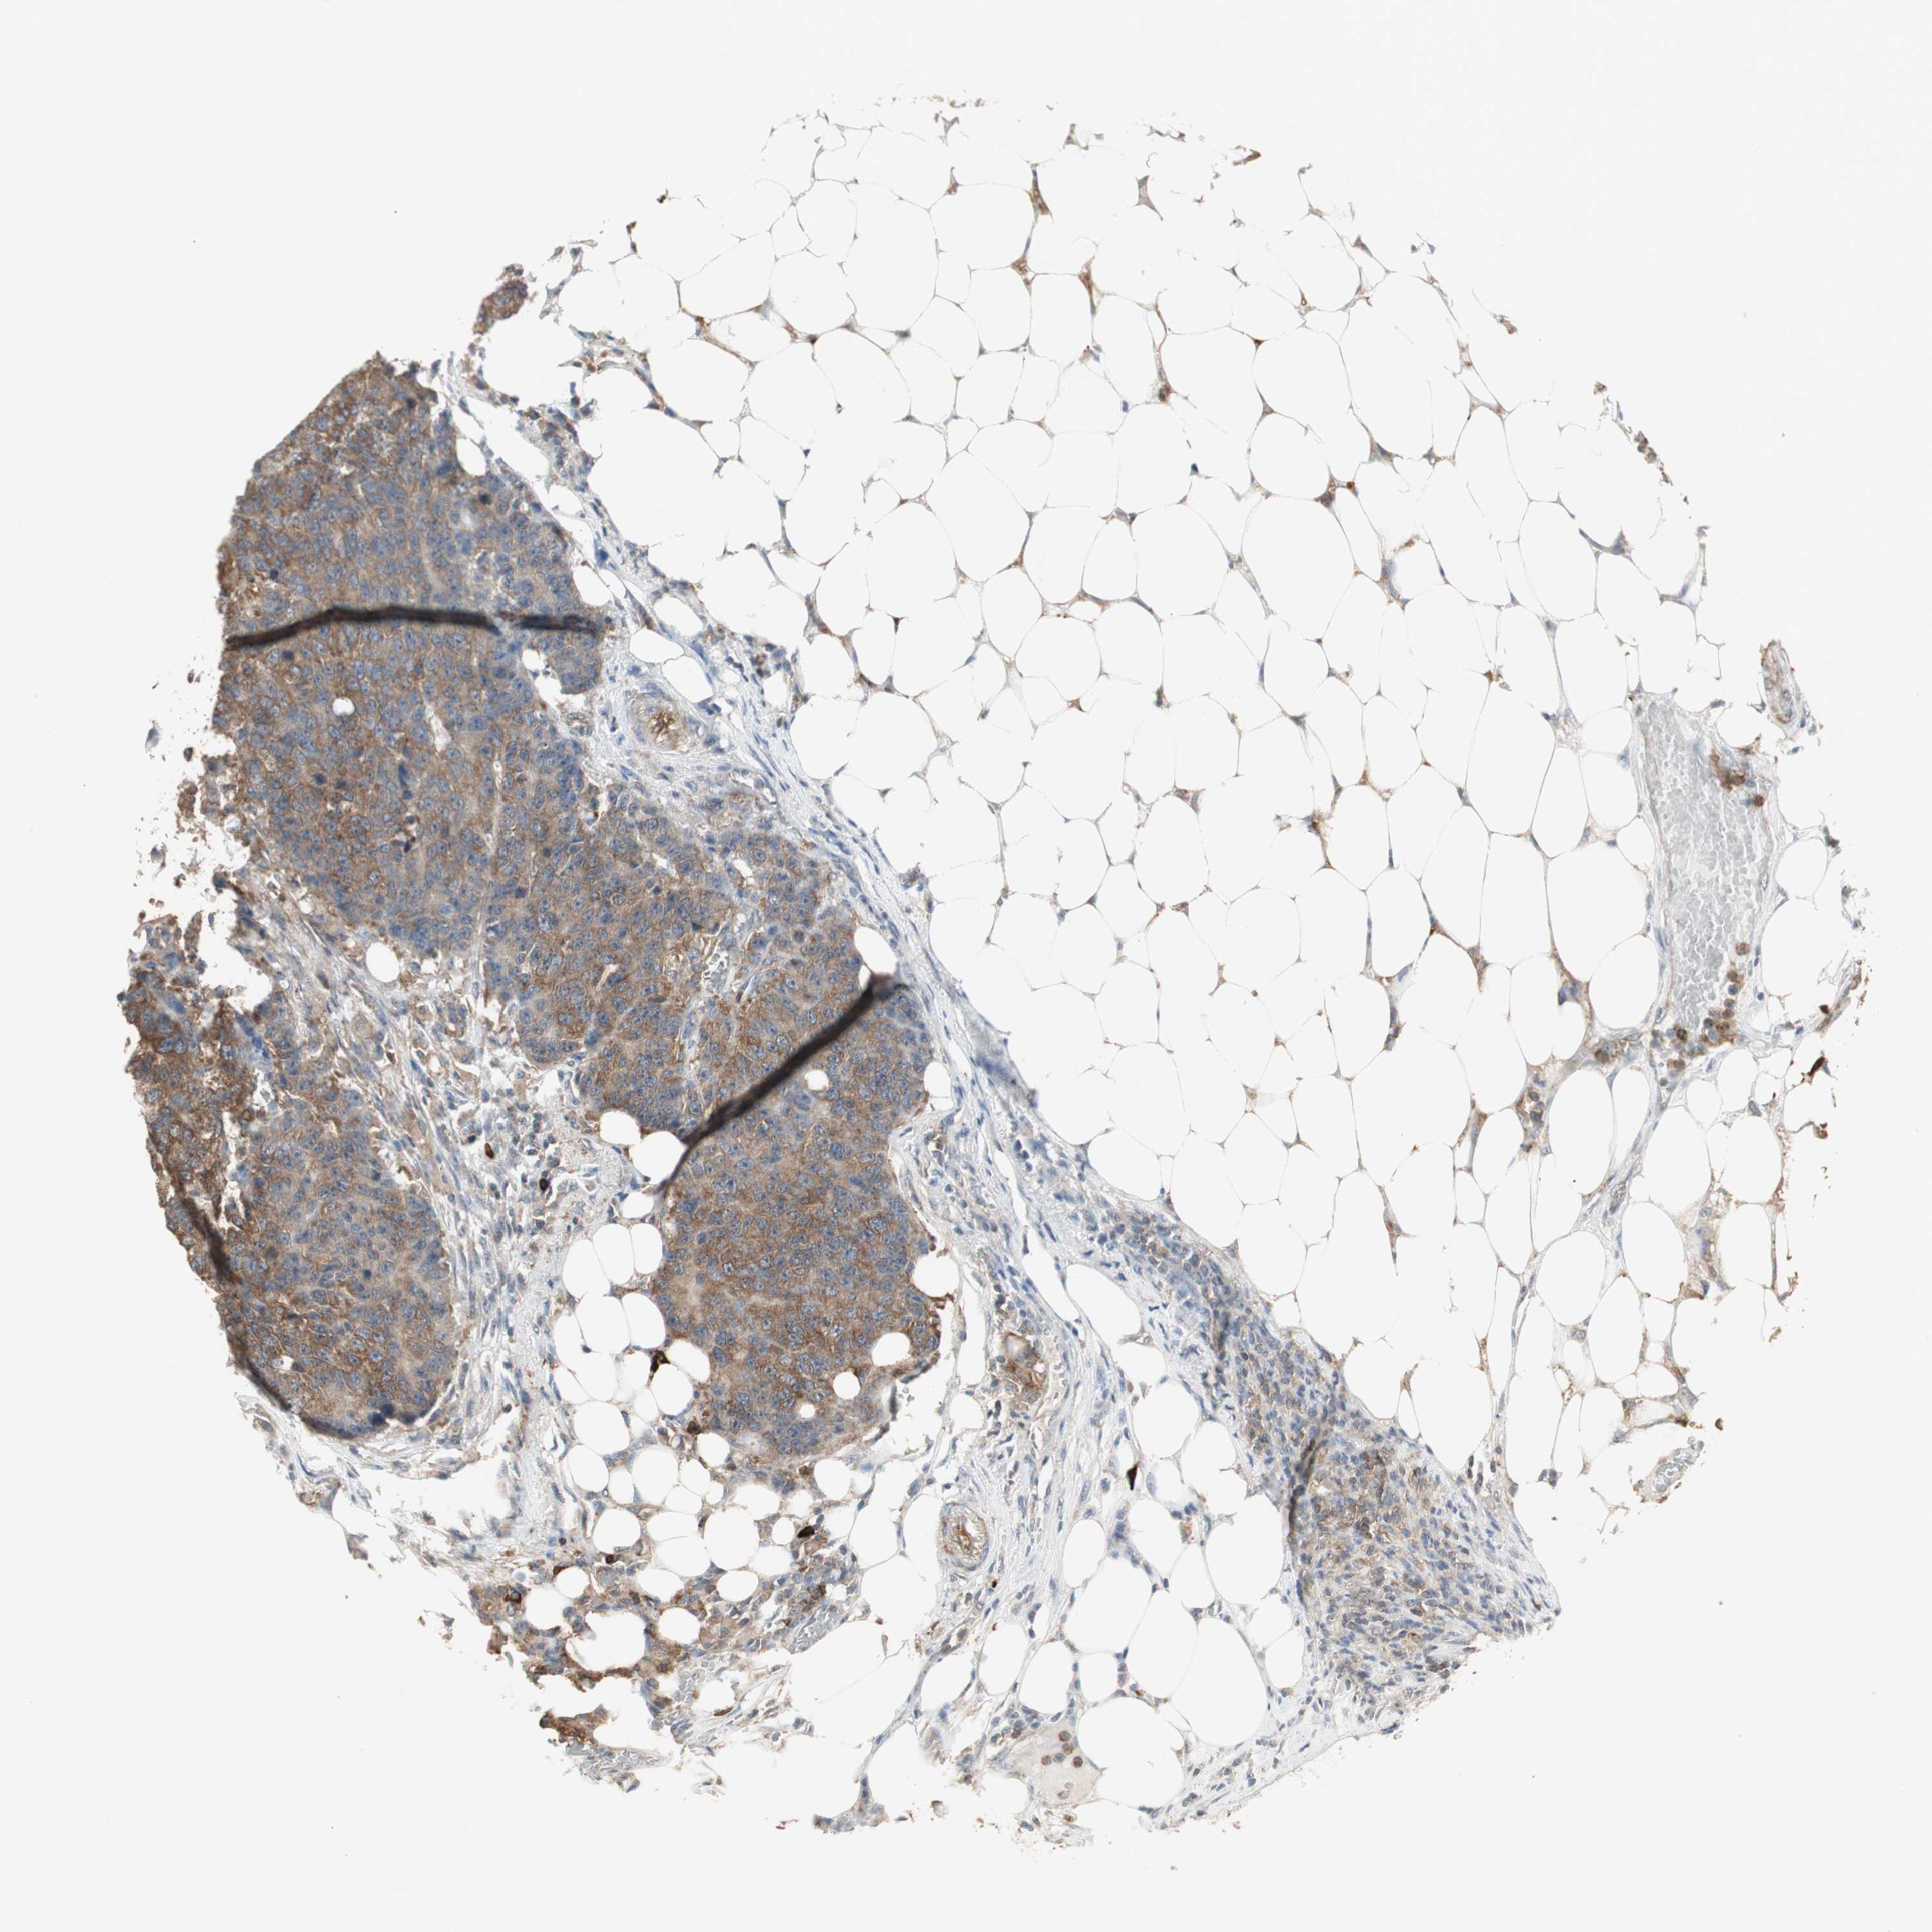

CANCER COLORECTAL CANCER Show tissue menu

Colorectal cancer

Human cancer

Colon adenocarcinoma

Rectum adenocarcinoma

COLON ADENOCARCINOMA (TCGA) - Interactive survival scatter ploti

The Survival Scatter plot shows the clinical status (i.e. dead or alive) for all individuals in the patient cohort, based on the same data that underlies the corresponding Kaplan-Meier plots. Patients that are alive at last time for follow-up are shown in blue and patients who have died during the study are shown in red.

The x-axis shows the expression levels (FPKM) of the investigated gene in the tumor tissue at the time of diagnosis. The y-axis shows the follow-up time after diagnosis (years). Both axes are complimented with kernel density curves demonstrating the data density over the axes. The top density plot shows the expression levels (FPKM) distribution among dead (red) and alive patients (blue). The right density plot shows the data density of the survived years of dead patients with high and low expression levels respectively, stratified using the cutoff indicated by the vertical dashed line through the Survival Scatter plot. This cutoff is automatically defined based on the FPKM cutoff that minimizes the p-score. The cutoff can be changed by dragging the vertical line or by entering a cutoff value in the square labeled "Current cut-off".

Under the Survival Scatter plot the p-score landscape (black curve; left axis) is shown together with dead median separation (red curve; right axis). Dead median separation is the difference in median mRNA expression between patients who have died with high and low expression, respectively. It is calculated as follows: median FPKM expression of dead patients with high expression - median FPKM expression of dead patients with low expression. This is intended to aid the user in visually exploring custom cutoffs and the associated p-scores and dead median separation.

Individual patient data is displayed and can be filtered by clicking on one or more of the category buttons on the top of the page. Categories describing expression level and patient information include: high, low, alive, dead, female, male and tumor stages. The scale of the x-axis can be toggled between linear and log-scale by clicking on the "x log" button. Mouse-over function shows TCGA ID, patient information and mRNA expression (FPKM) for each patient.

& Survival analysisi

Kaplan-Meier plots summarize results from analysis of correlation between mRNA expression level and patient survival. Patients were divided based on level of expression into one of the two groups "low" (under cut off) or "high" (over cut off). X-axis shows time for survival (years) and y-axis shows the probability of survival, where 1.0 corresponds to 100 percent.

MMP3 is not prognostic in Colon Adenocarcinoma (TCGA)

Best expression cut offi

Based on the FPKM value of each gene, patients were classified into two groups and association between prognosis (survival) and gene expression (FPKM) was examined. The best expression cut-off refers the FPKM value that yields maximal difference with regard to survival between the two groups at the lowest log-rank P-value. Best expression cut-off was selected based on survival analysis .

When clicking on this number, the vertical dashed line indicating cut-off, the interactive survival plot, and the Kaplan-Meier curve will be adjusted to show results based on the best expression cut-off.

: 8.59

P scorei

Log-rank P value for Kaplan-Meier plot showing results from analysis of correlation between mRNA expression level and patient survival.

N/A

5-year survival highi

5-year survival for patients with higher expression than the expression cutoff.

For melanoma and glioma, 3-year survival is shown.

5-year survival lowi

5-year survival for patients with lower expression than the expression cutoff.

TCGA RNA samplesi

RNA-seq data is reported as average FPKM (number Fragments Per Kilobase of exon per Million reads), generated by the The Cancer Genome Atlas (TCGA) .

Normal distribution across the dataset is visualized with box plots, shown as median and 25th and 75th percentiles. Points are displayed as outliers if they are above or below 1.5 times the interquartile range. FPKM values of the individual samples are presented next to the box plot.

Average pTPM 41.4

Number of samples 254